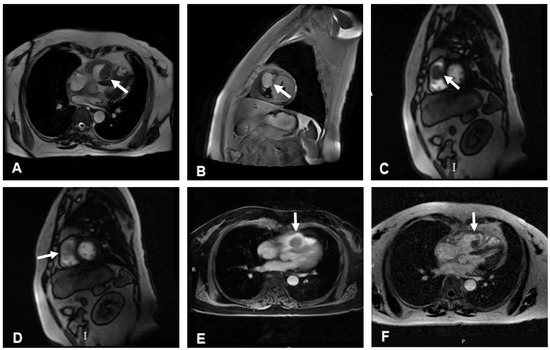

A right ventricular mass was accidentally identified in a 56-year-old woman during chest CT for a respiratory infection at a local hospital. Transthoracic echocardiogram (TTE) revealed a cardiac mass, and the patient was admitted to our hospital for further diagnosis and treatment. The patient had a history of hypertension but no history of coronary artery disease. A grade 2/6 systolic murmur was heard between the second and third intercostal spaces at the left sternal border. The electrocardiogram showed sinus rhythm with possible right bundle branch block, and chest X-ray revealed a normal-sized heart. TTE indicated that the right ventricle was of normal size. A 43 × 28 mm mass with a moderate echo appearance, neither mobile nor pedunculated, was found to be adherent to the interventricular septum and extended to the right ventricular outflow tract. In addition, mild tricuspid regurgitation and normal mitral and aortic valves were noted (Figure 1).

Figure 1.

Transthoracic echocardiography of the lesion. (A) A 43 × 28 mm mass with medium echo appearance, neither mobile nor pediculated, adhering to the interventricular septum and extending to the right ventricular outflow tract. (B) Color Doppler flow imaging (CDFI): no significant blood flow signal was detected in the mass, and slight aliasing was noted in the right ventricular outflow tract.